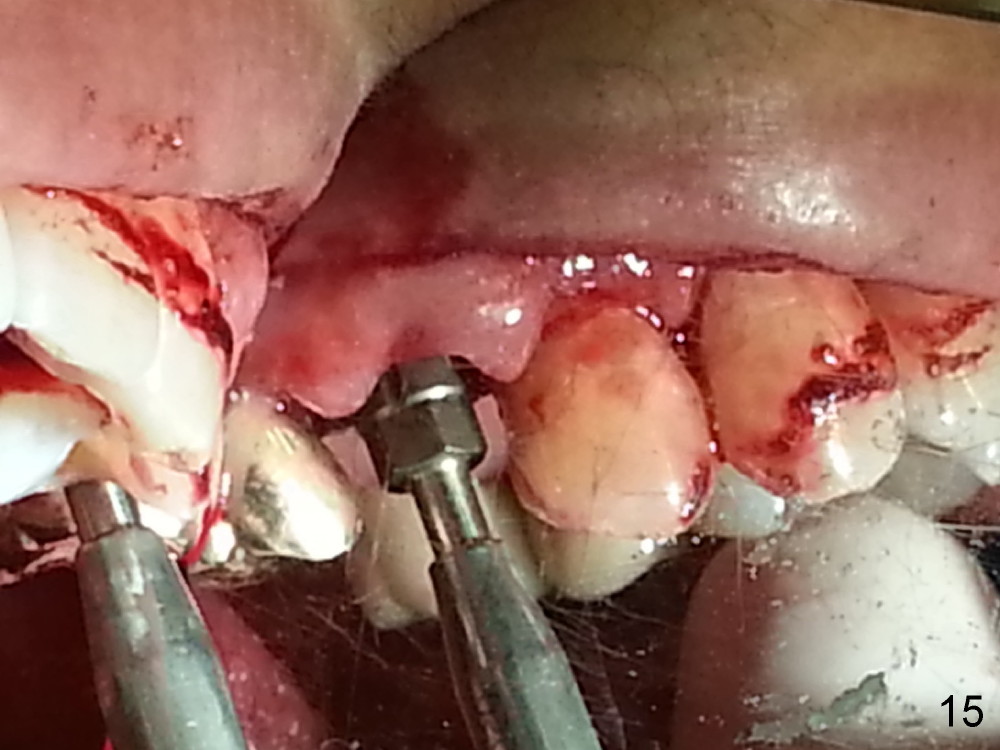

Grafting Following Immediate Implant (Photos Provided by Xue Steven, DDS)

The tooth #13 appears to be affected by periodontits and occlusal trauma (Fig.1*). After using a periotome (Fig.2), the tooth is extracted (Fig.3). The buccal flap is raised (Fig.4). Gingival graft is to be harvested from the site of #15 (Fig.5). The tissue is elevated buccally (Fig.6) and separated (Fig.7). The donor site is covered by a collagen membrane (Fig.8*). A diamond bur is used to induce bleeding from the socket (Fig.9*). Osteotomy is initiated (Fig.10) and enlarged (Fig.11,12). A tapered implant is being placed (Fig.13-15) following internal sinus lift (Fig.16,17). The implant is placed subcrestally, followed by bone graft (Fig.18), soft tissue graft (Fig.19), and suturing (Fig.20 <, Fig.21).